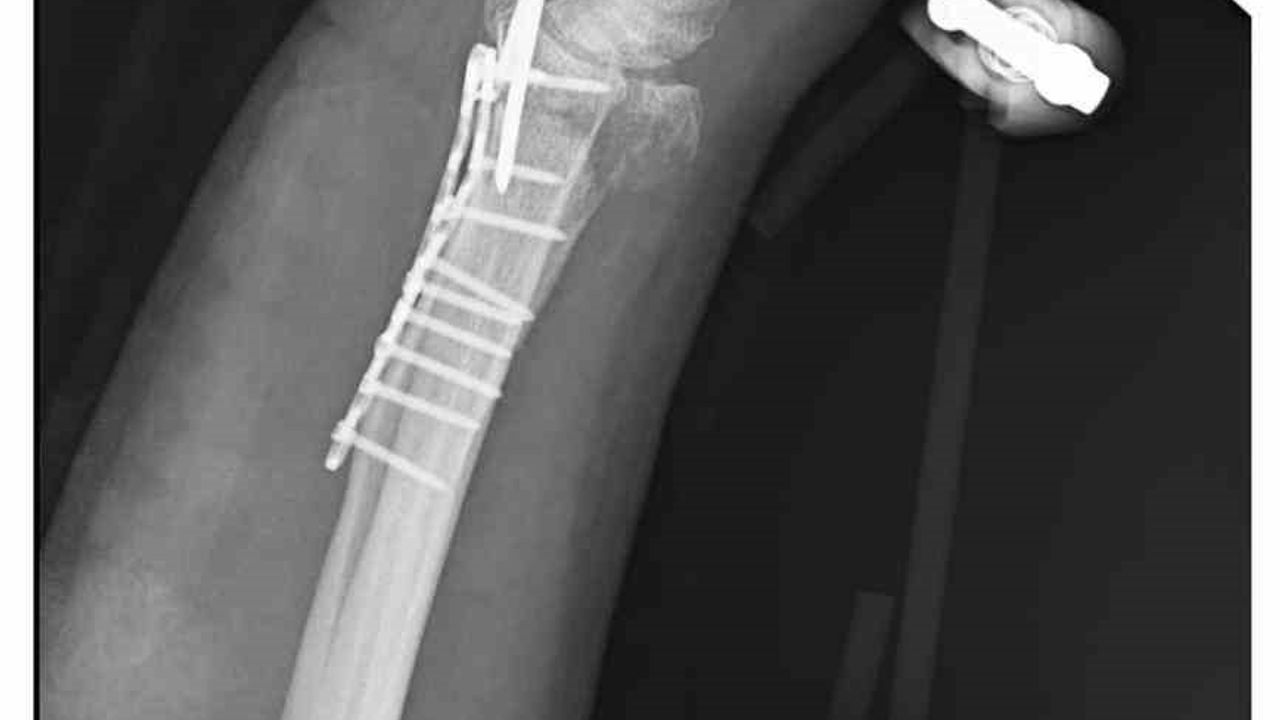

Olay, 29 Aralık günü Mamak'ta meydana geldi. Alınan bilgilere göre, 35 yaşındaki Yasin Arslantaş yaşadığı apartmanın önünde yaklaşık 10 sahipsiz köpek tarafından kovalandı. Kaçmaya çalışırken düşerek el bileği kırılan Arslantaş, ambulansla hastaneye kaldırıldı. Bilek kemiğine 11 adet platin takılan Arslantaş'ın kolunda kalıcı his ve hareket kaybı meydana geldi. Olay nedeniyle maddi ve manevi açıdan zor zamanlar geçirdiği söyleyen Arslantaş, belediye ekiplerinin yaşanan soruna hala çözüm üretmediğini iddia etti.

'Bileğimde 15 dikiş ve 11 platin var'

Yasin Arslantaş, 'Sabah apartmandan çıkış yaptığım sırada arkamdan 9 köpeğin geldiğini gördüm. Saldırgan haldelerdi. Bana saldırmak üzerelerdi. Kaçmaya çalışırken ayağım kaydı ve düştüm. Bileğimde 15 dikiş ve 11 platin var. İki ay boyunca kolum bu halde kalacak ve ardından da yine 2 buçuk ay fizik tedavi süreci olacak. Doktorlar his ve hareket kaybımın olacağını söylediler. Bileğimden büyük kemiğin kırılmasından dolayı zorlu bir süreç geçiriyorum. 3 saatlik bir ameliyat geçirdim' dedi.